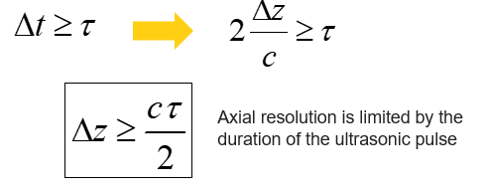

Axial Resolution

The Axial Resolution is the minimum distance that can be differentiated between two reflectors located parallel to the direction of the ultrasound beam.

Mathematically, it is equal to half the spatial pulse length.

However, the Axial resolution is limited by the duration of the ultrasonic pulse. It is high when the spatial pulse length is short.

The axial resolution or the resolution in the direction of the axis of the ultrasonic beam depends on the duration of the ultrasonic pulse.